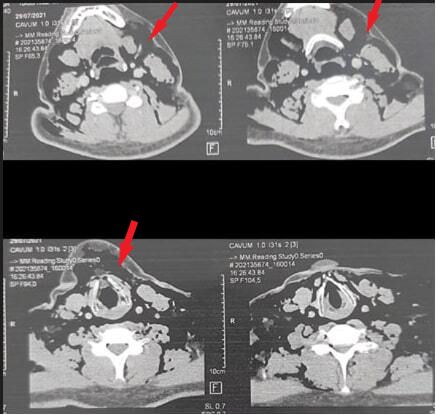

Four days after admission, the patient presented with tachycardia and cervical tumefaction. Physical examination showed a crepitus on palpation over the neck and an audible crunchy sound on cardiac auscultation. Repeat CT-Scan showed extensive cervical anterior emphysema with pneumomediastinum without pneumothorax (Figure 1 and 2). Cardiothoracic surgery was consulted and they recommended a closely monitoring of the clinical status of the patient. Surgical intervention was unnecessary. The patient was observed and his respiratory status improved slowly but continuously. The oxygen requirements decreased. Repeat CT-Scan showed a favourable outcome (Figure 3).